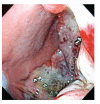

Primary gastric melanoma: a rare cause of upper gastrointestinal bleeding